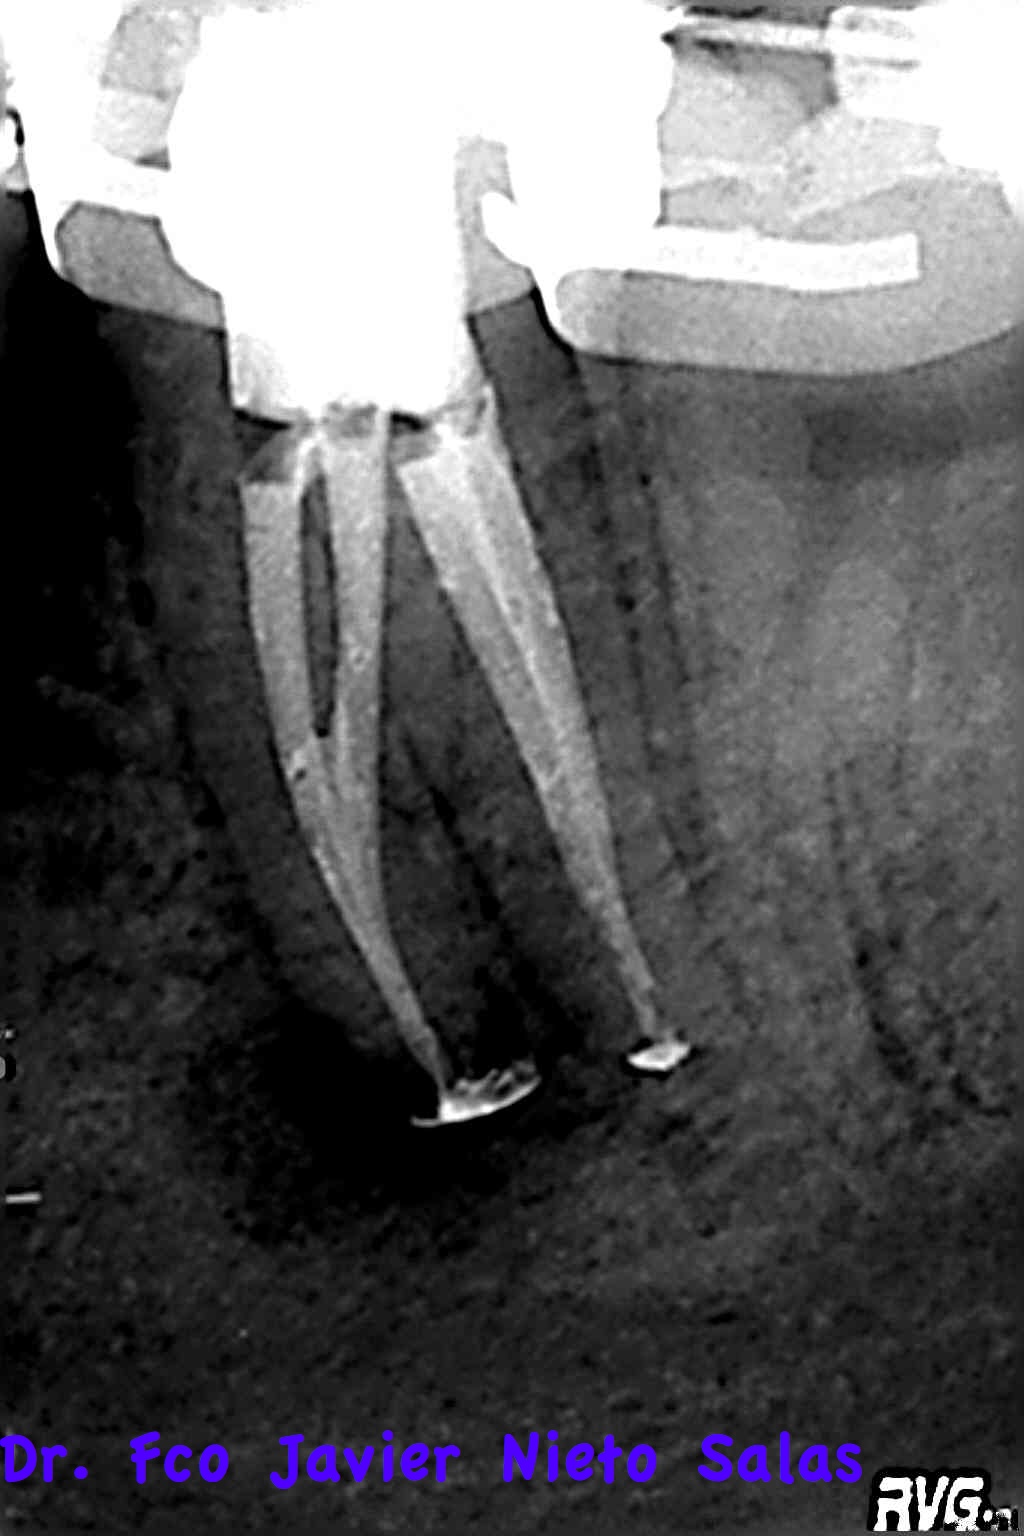

Presentaba una lesión periapical crónica, su diagnóstico es una necrosis pulpar con periodontitis apical crónica.

Le realizamos el tratamieto endodóntico del sistema de conductos en dos sesiones, soy un fiel defensor del medicameento intraconductos por varios motivos que quizás no sea el momento de comentar.

Usamos la técnica de ola continua de calor descrita por Buchanan y el backfilling se hizo con gutapercha inyectada.